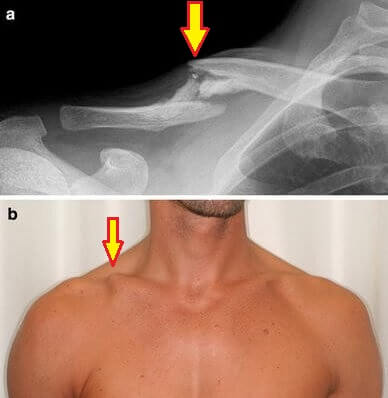

The most common cause of a hard lump on the collarbone is a clavicle fracture.

A clavicle fracture is where there is a break in the collarbone. There may be a small hairline fracture, a complex fracture with multiple breaks or anything in between.

In the longer term, you may end up with a small, permanent hard lump on the collarbone following a clavicle fracture. As the broken bone heals, the body lays down extra bone to knit the bones back together and in some cases, excess bone can form around the fracture site known as bone spurs or osteophytes. These hard lumps on the clavicle don’t usually cause any problems unless the break was close to the joint in which case it may slightly reduce shoulder range of motion.

A hard lump on the collarbone usually indicates a bone problem such as a clavicle fracture, ACJ dislocation or bone spurs.

A broken collarbone bump is usually associated with either a contact injury or a fall and causes immediate localised pain. Shoulder movement is usually limited and there may be an obvious deformity.